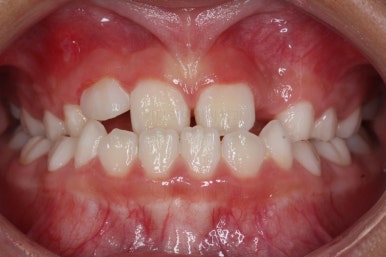

유지단계 11개월 경화 후의 모습입니다. 유지상태는 상당히 좋네요.

이제 유지장치도 종료하기로 하고, 앞으로는 주기적으로 아래턱이 자라나지 않는 지를 체크하게 될거에요.